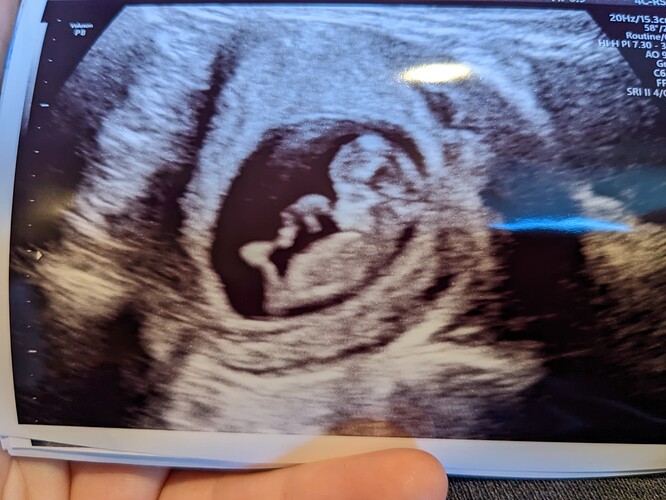

Second scan looks good! I’m honestly shocked. Also was so not prepared for it to MOVE.

Pics and stats below.

Heart rate 165, 3.7cm. 10 weeks 4 days.